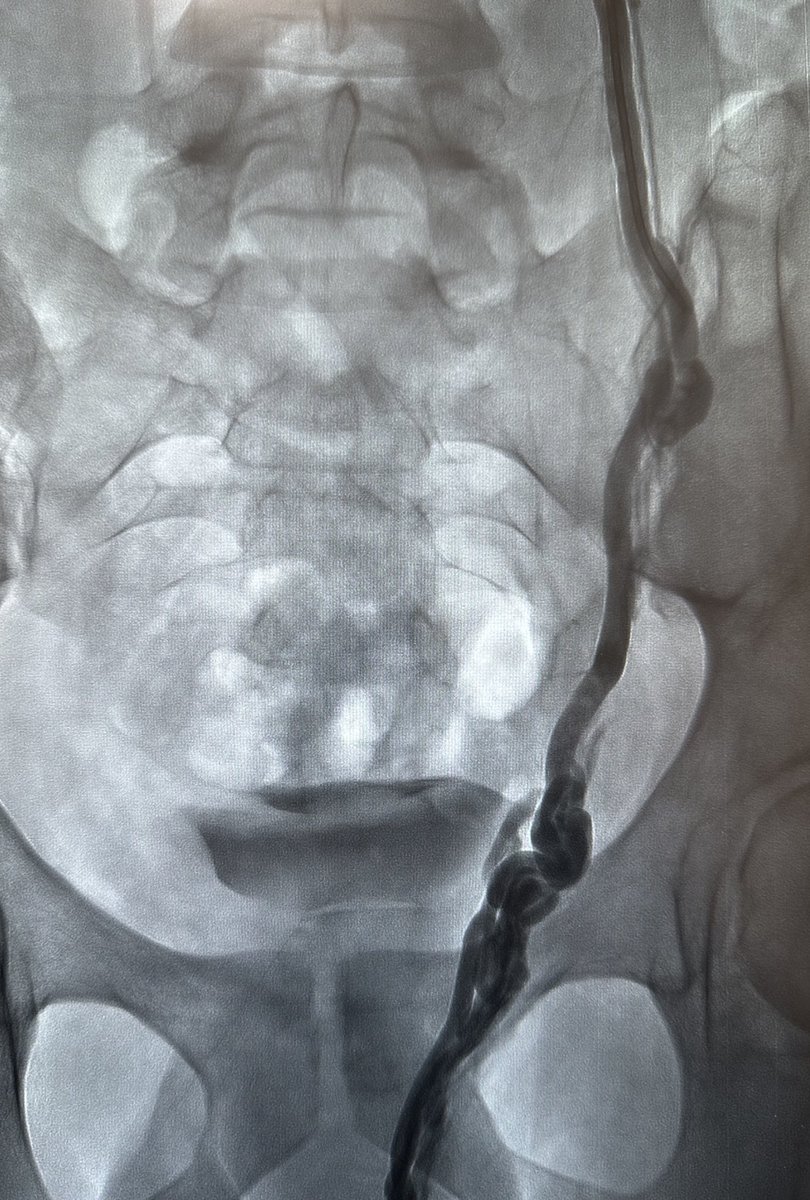

علاج دوالي الخصية بالأشعة التداخلية ، العلاج بالصمغ الطبي يعتبر أفضل وأحدث علاج. يتم إغلاق الدوالي والأوردة بدقة دون التعرض للشرايين والقنوات الليمفاوية الدقيقة. مثال لمريض لديه ما يفوق عن ٤٠ وريد ، لا يمكن ربطها جميعاً جراحياً. بالقسطرة؟ انتهينا من الجهتين خلال اقل من ١٠ دقائق.

طريقة تغلغل الصمغ الطبي في علاج الأوردة المغذية لدوالي الخصية بالقسطرة. اغلاق جميع الأوردة بدون المساس بالقنوات الليمفاوية (فلا يحصل قيلة مائية) ولا الشعيرات الشريانية الدقيقة (فلا يحصل ضمور) القسطرة والأشعة التداخلية اثبتت بالابحاث افضليتها على الجراحة من كل النواحي